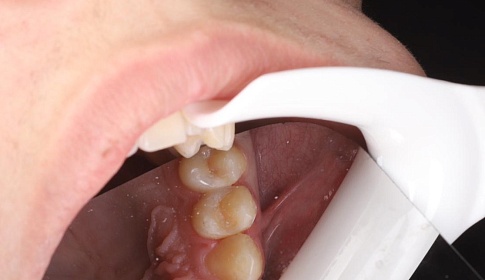

Пломбирование и восстановление коронковой части зуба при лечении среднего и глубокого кариеса выполняются композитными фотополимерными материалами лучших производителей из Японии (Эстелайт), США (Филтек), Германии (Динамик, Дайракт), Италии (Геркулайт).

Материалы обладают великолепными характеристиками (повышенная износоустойчивость, большое разнообразие оттенков, пластичность), которые позволяют стоматологу успешно восстанавливать функциональные и эстетические параметры зуба. Используемый пломбировочный материал универсален, нетоксичен, гипоаллергенен, с равным успехом применяется для установки пломб на зубах взрослых и детей.